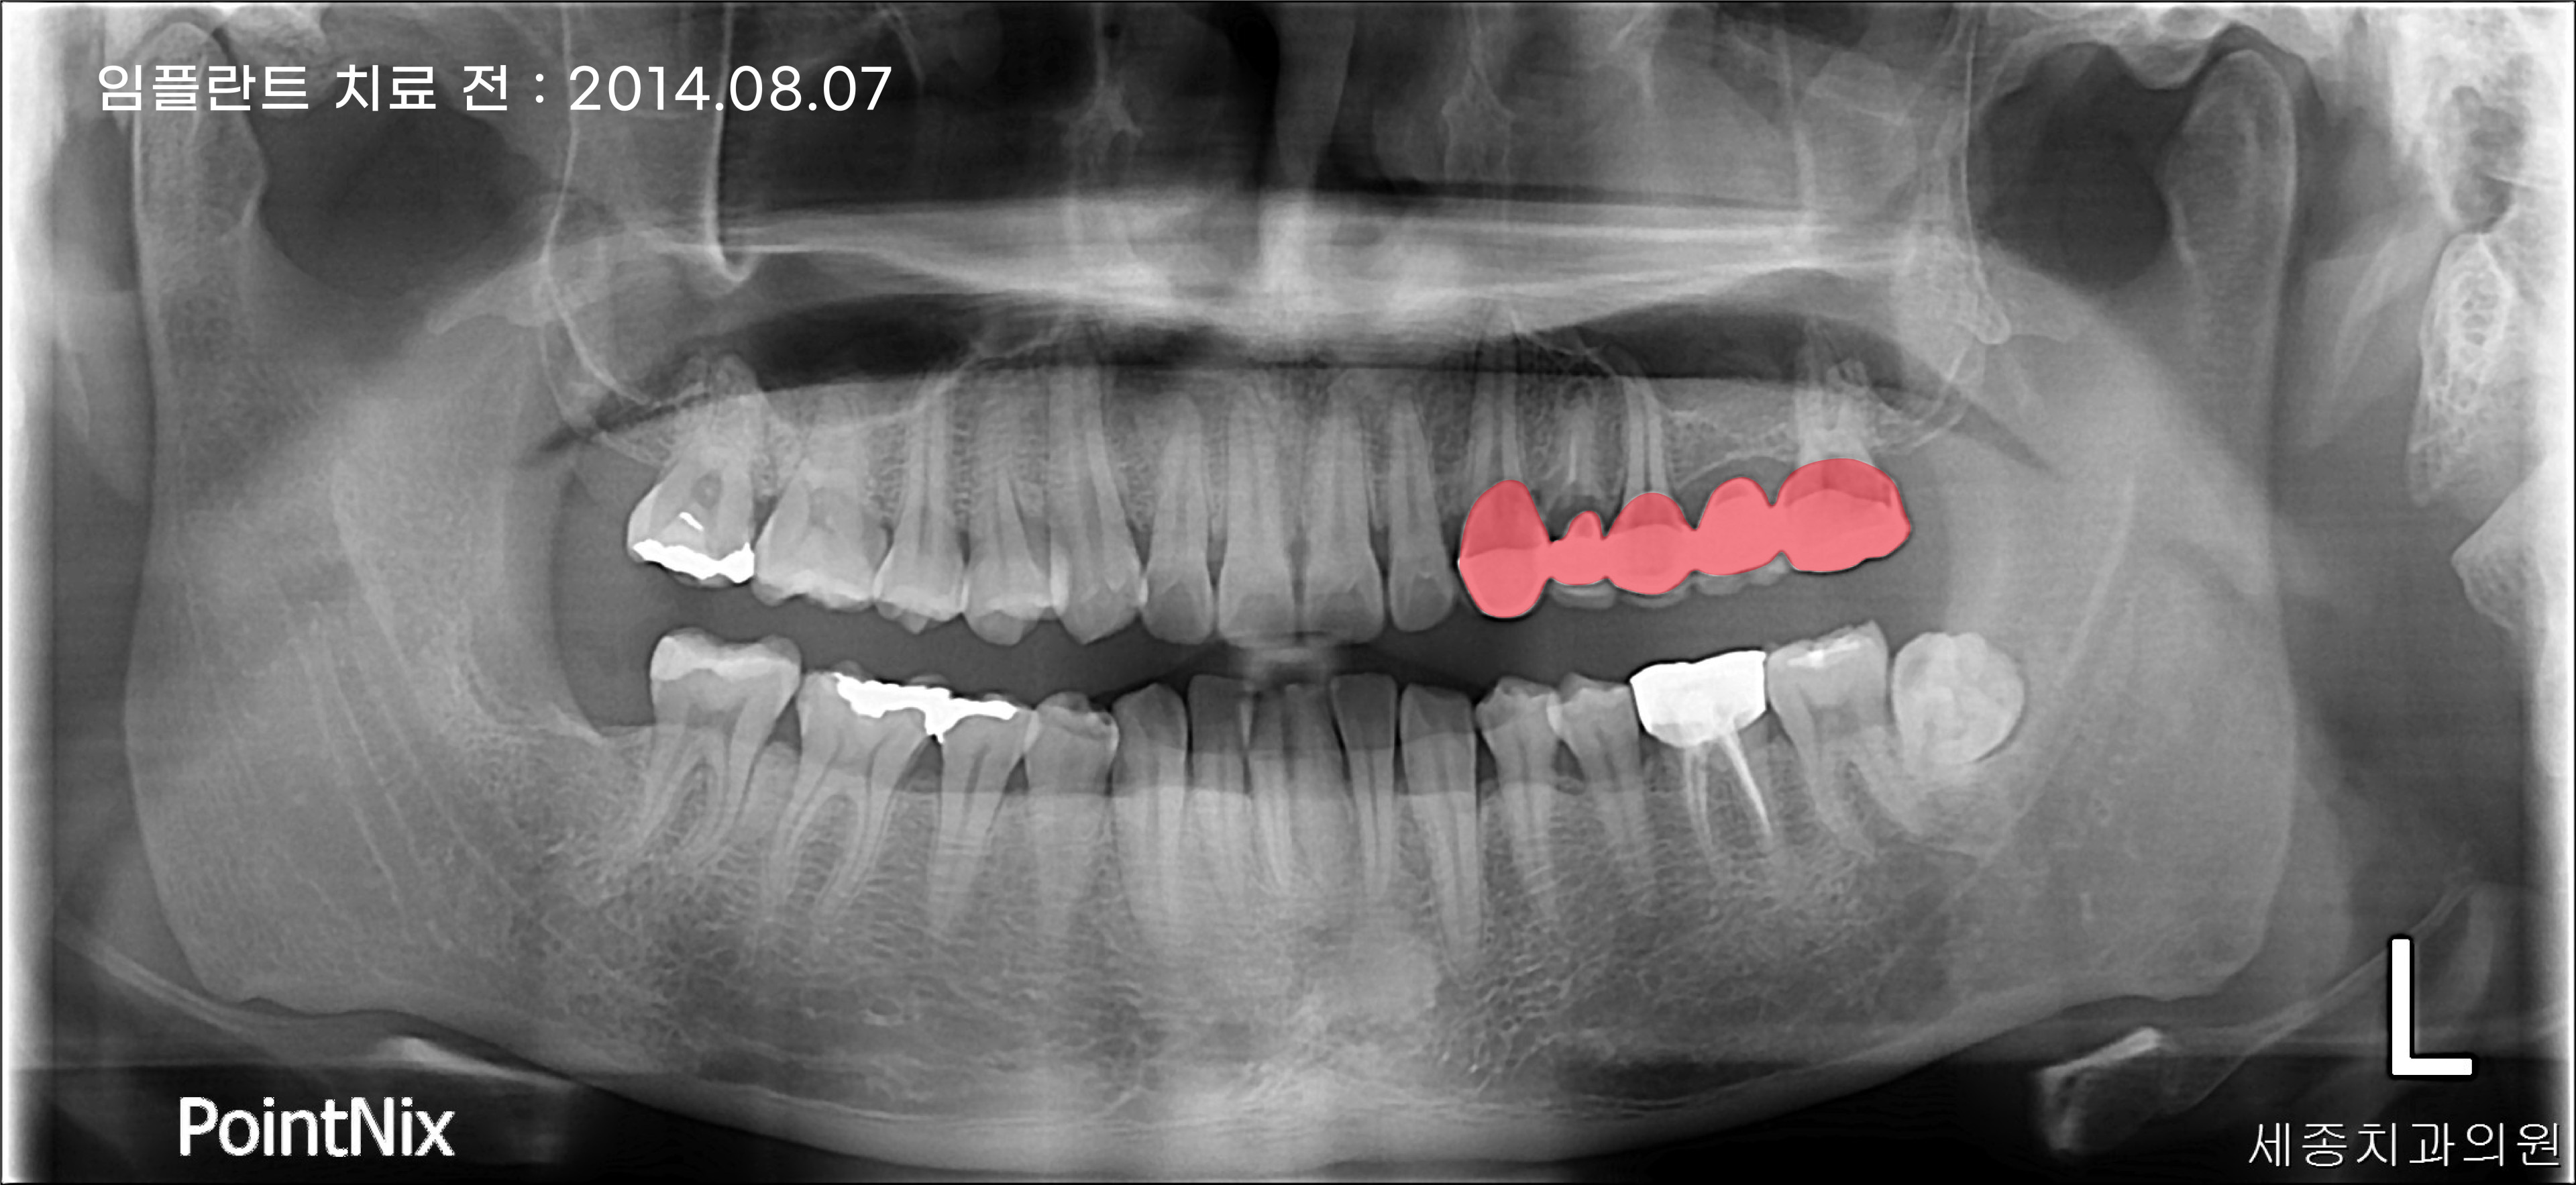

환자분께서 부산임플란트잘하는곳 세종치과에

처음 내원하셨을때 찍은 파노라마입니다.

좌측 상악 부분에 빨갛게 표시된 5개의 보철물이 문제를 유발하는 원인이었는데요.

자세히 살펴보니 보철 밑에 충치가 나타난것을 확인할 수 있었습니다.